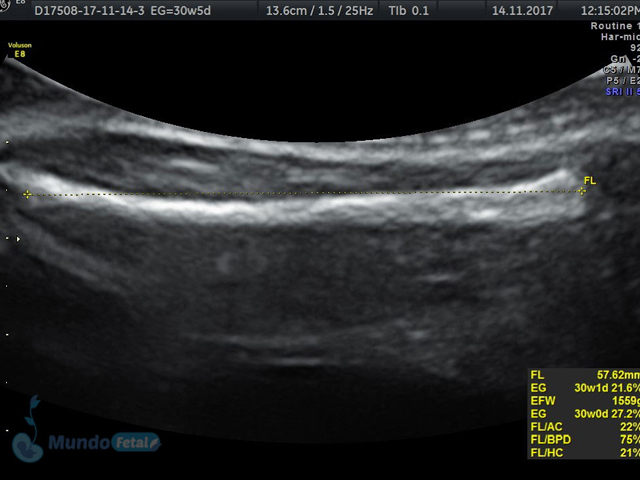

Se recomienda de 32-34 semanas, realizando valoración de crecimiento armónico (4 medidas específicas), valoración anatómica, líquido amniótico, flujos sanguíneos fetales y placentarios perfilando el bienestar fetal hacia el final de embarazo.